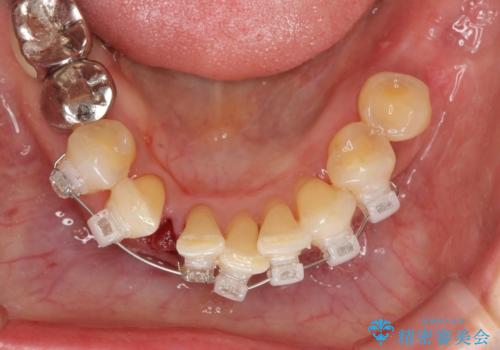

通常 抜歯後はインプラントやブリッジといった方法で欠損部位の機能や審美性を回復しますが、今回は臨在する歯のガタつきも利用し上下の歯を矯正治療することで人工物を装着することなく歯を並べます。

矯正治療を行うことで、歯を削ったり(ブリッジ)、手術の必要(インプラント)なく機能を欠損部位を無くし機能回復を達成することができました。